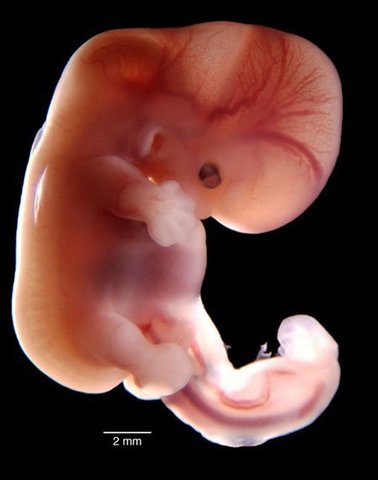

• SEMANA 4

SEMANA 4

Corazón empieza a latir.

el primer aparato que comienza a funcionar es el sistema circulatorio.

semana 3- 4 se evidencia un plano del cuerpo.

Crecimiento cerebral.

Desarrollo de extremidades superiores.